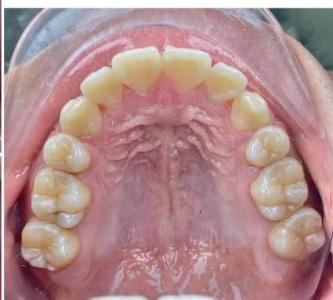

### b) Intraoral Examination

Intraoral examination revealed severe proclination and protrusion of both the maxillary and mandibular incisors [6]. The occlusal relationship was Class I at the canine (tooth 3) and first molar (tooth 6) levels bilaterally. A critical unfavorable biological factor was the proximity of the mandibular incisor roots to the labial cortical plate, representing a high-risk condition when planning extraction-based anterior retraction mechanics [10-12]. All four third molars were present.

Figure 2: Pre-Treatment Intraoral Photographs